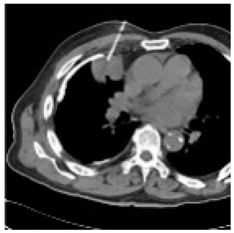

| Original Medical Images | |||||||

| Pair 1 | Pair 2 | Pair 3 | Pair 4 | ||||

![]() (1-9) PSNR = 44.14 | ![]() (1-10) PSNR = 41.90 | ![]() (1-11) PSNR = 40.09 | ![]() (1-12) PSNR = 41.41 | ![]() (1-13) PSNR = 42.24 | ![]() (1-14) PSNR = 40.35 | ![]() (1-15) PSNR = 40.79 | ![]() (1-16) PSNR = 40.84 |

| Shadow Images Produced by Using LSBs | |||||||

![]() (1-17) PSNR = 26.35 | ![]() (1-18) PSNR = 25.49 | ![]() (1-19) PSNR = 23.57 | ![]() (1-20) PSNR = 24.19 | ![]() (1-21) PSNR = 24.79 | ![]() (1-22) PSNR = 24.23 | ![]() (1-23) PSNR = 23.26 | ![]() (1-24) PSNR = 24.42 |

| Shadow Images Produced by Using Middle Bits | |||||||

![]() (1-25) PSNR = 18.97 | ![]() (1-26) PSNR = 19.95 | ![]() (1-27) PSNR = 14.10 | ![]() (1-28) PSNR = 13.84 | ![]() (1-29) PSNR = 16.66 | ![]() (1-30) PSNR = 13.23 | ![]() (1-31) PSNR = 13.38 | ![]() (1-32) PSNR = 14.75 |

| Shadow Images Produced by Using MSBs | |||||||